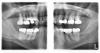

A 38-year-old female patient with incipient decay discovered on a transillumination caries detection device image (Figure 5 and Figure 6) presented for her bi-annual hygiene visit. The doctor was considering whether to treat the decay with a restoration or to "watch it." He decided that instead of monitoring the lesion, he could treat it with silver diamine fluoride, possibly halting the decay and hardening the lesion. The patient was informed of the possibility the decay would turn black; however, the decay process could halt, and she would not need a filling in the future. She was pleased at the prospect her tooth would remain intact without needing restorative treatment. After signing the consent form, she opted for treatment that day in the hygiene visit. She was appointed for one week later for the re-application of the silver diamine fluoride and advised that it may need to be reapplied one to two times per year.

(5.)  Incipient decay on tooth No. 29.

Figure 5

(6)  Incipient decay on tooth No. 20.

Figure 6